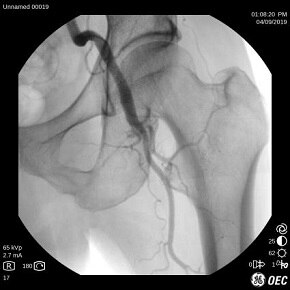

Ангиография бедренной артерии, 21 см